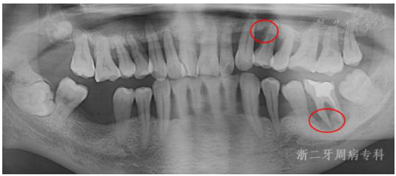

口腔卫生欠佳,软垢指数:2;牙石指数:3;全口牙龈充血红肿;平均牙周探诊深度(PD)7.0 mm,PD≥7 mm的位点占所有检查位点的63.3%(114/180),其中17颊侧远中、17舌侧远中、34舌侧远中、36颊侧近中、46舌侧近中PD深达12 mm;平均附着丧失(CAL)9.3 mm、CAL≥5 mm的位点数为98.3%(177/180);BOP(+)%:100%;37、46松动度Ⅲ度,11~17、21、22、24~27、32、34、41~43、45、47松动Ⅱ~Ⅲ度,余牙松动度Ⅰ度;36、46Ⅲ度根分叉病变。16、26、36、46牙釉质发育不Ⅲ全,11扭转,37缺失舌向倾斜,12、14~16、24、25、41、42咬合时出现异常动度,31、41可见1.5 mm左右牙间隙(图1,图2)。牙髓活力测定:17、34牙髓活力正常,36、37、46"40"无反应。

全口曲面体层X片示:全口牙槽骨广泛性水平吸收,46牙槽骨吸收超过根尖;36根尖周和根分叉区低密度影;13、22、23、33~35、43~45、47牙槽骨吸收达根长1/2~2/3,余牙牙槽骨吸收至近根尖(图3)。